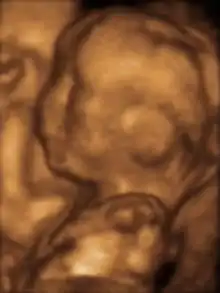

A 3D ultrasound (image)

- (uncountable) A medical ultrasound technique, used, for example, during pregnancy, providing three-dimensional-looking flat images.

- (countable) An image so produced.